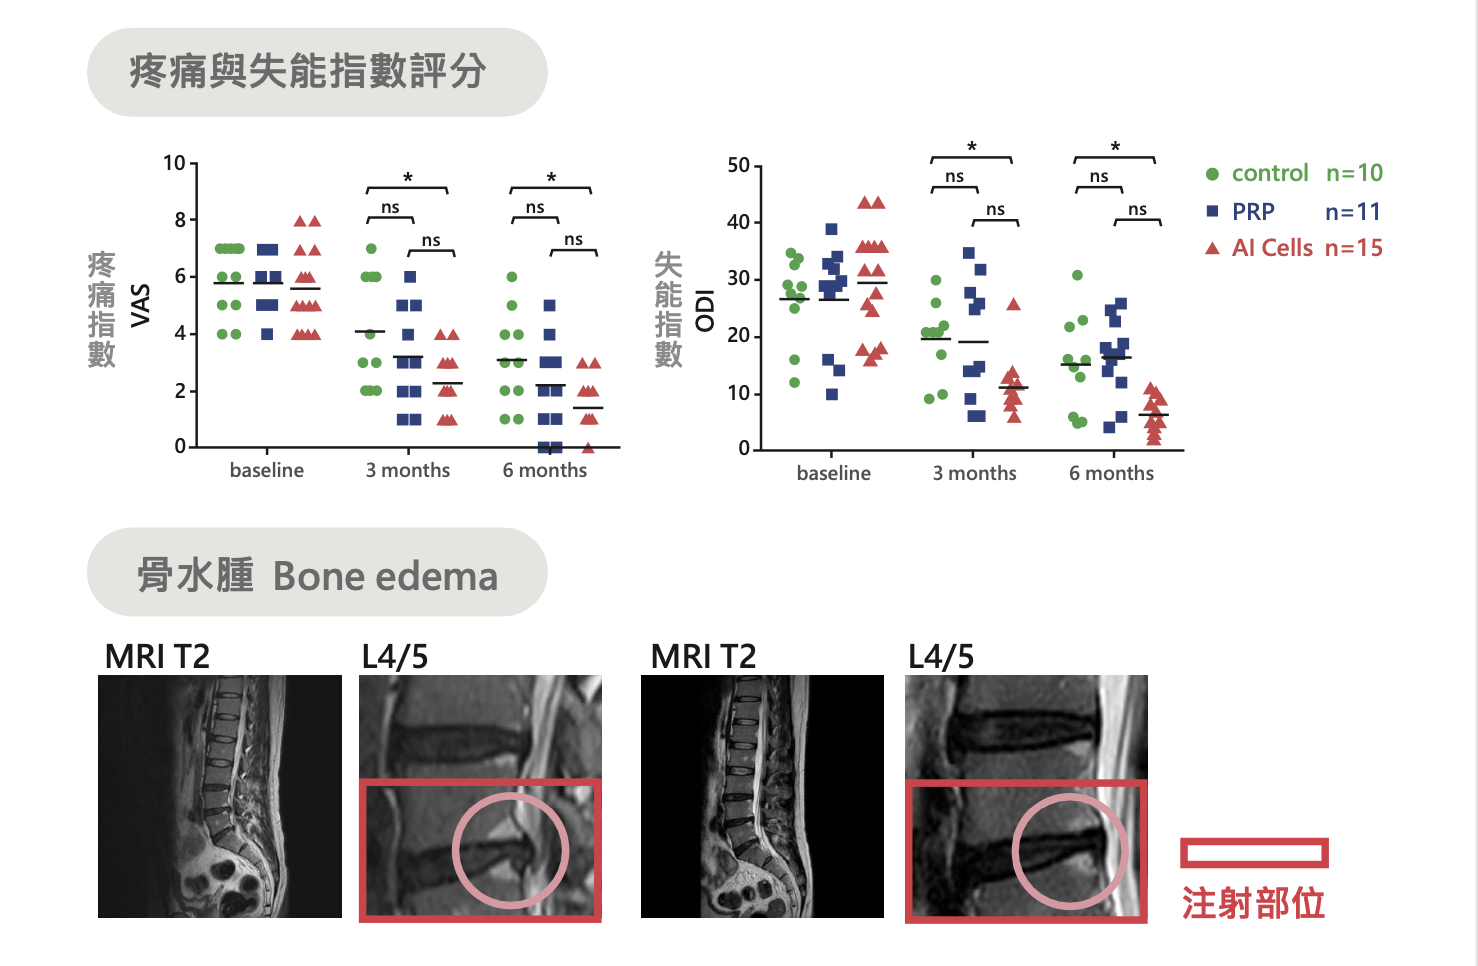

椎間盤退化臨床成果

在椎間盤退化相關資料中,AI Cells 可有效降低椎間盤退化患者的疼痛,改善功能損失並減輕骨水腫。圖中可見疼痛指數(VAS)與失能指數(ODI)於治療後有下降趨勢,同時 MRI 影像也呈現骨水腫改善情況。

另一組比較圖則顯示,相較對照組與 PRP 組,AI Cells 組在維持髓核結構完整性方面表現較佳,對椎間盤退化源性疼痛提供了另一種治療評估方向。